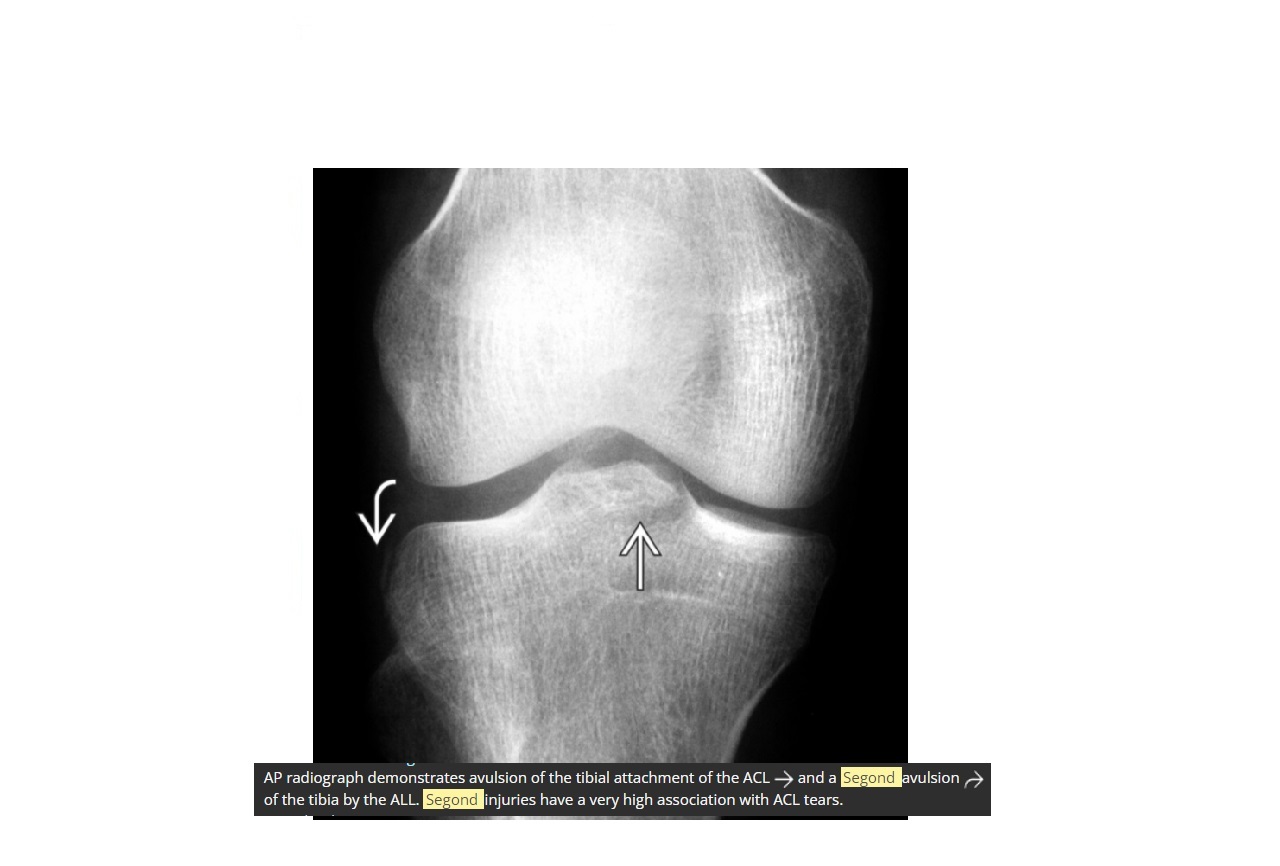

Segond fracture

Lateral tibial plateau

Associated with ACL tear (75%) and internal rotation

MR SL = Medial Reverse Lateral Segond

Reverse Segond fracture

Medial tibial plateau

Associated with PCL tear with external rotation. Associated with medial meniscus injury.